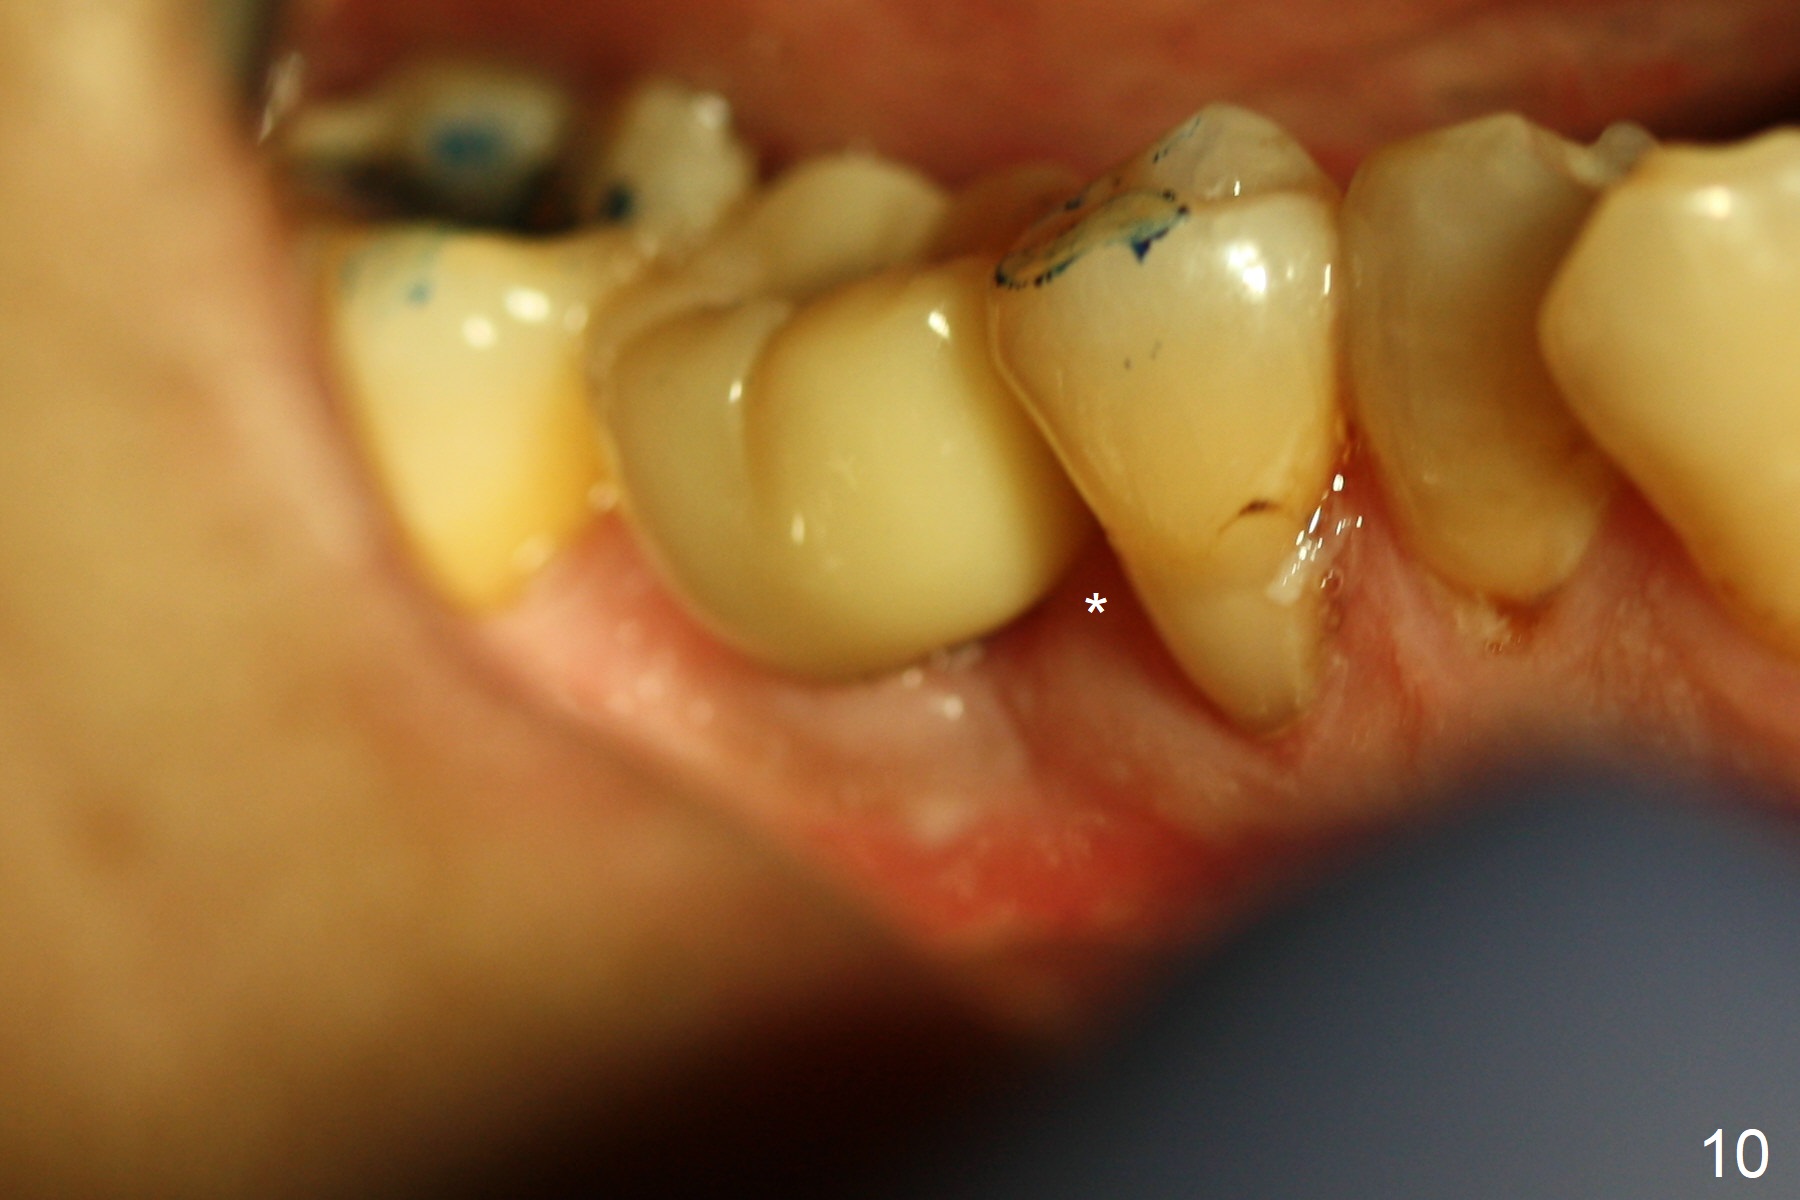

After extraction of the tooth #30, the mesiobuccal plate is found to be lost, corresponding to the fistula (Fig.1 <). Osteotomy is initiated in the flattened septum (lingual) for 13 mm (Fig.2). The patient feels pain when larger drills are being used. Marcaine has to be injected in an infiltration manner for pain control. When a 4.5x10 mm dummy implant is inserted with 55 Ncm, the end of the osteotomy (Fig.3 white line) is close to the Inferior Alveolar Canal (red dashed line). When a definitive implant (Fig.4: 4.5x11.5 mm) is placed with primary stability, there is an apical space (Fig.5 white double arrows). There is moderate postop pain. A shorter implant (10 mm) should be tried when the bone is dense. It will be associated with less pain. The fistula disappears 7 days postop (Fig.6). Although the patient appreciates that the pain is gone, there is atrophy mesiobuccally 2 months postop (Fig.7 *). The implant seems to be have been placed too buccally (Fig.8). With loss of the buccal plate, the implant should be placed away from it to prevent periimplantitis. The abutment is changed from 6.5x4(4) to 6.5x5.5 (3) mm with fabrication of a new provisional. The buccal margin is still supragingival 6 months postop and prep lower before impression. The mesial and distal sockets appear to have healed (Fig.9). When the crown is cemented, the mesiobuccal papilla is present (Fig.10 *), while the mesiolingual one is apparently absent (Fig.11 *). Using a temporary abutment and relining the provisional multiple times would increase the chance of rebuilding the missing papilla. The bone density around the implant increases 11 months post cementation (Fig.12). The dense (apparently cortical) bone seem to grow over the implant plateau 11 months post cementation (Fig.13 <).